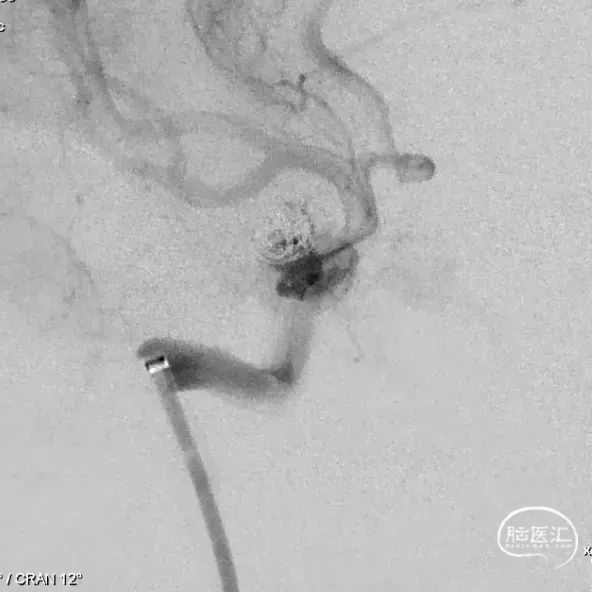

外院DSA

右侧颈内动脉眼动脉段-海绵窦段串联两枚动脉瘤,分别大小约:

① 8.8mm*5.9mm*5.2mm,瘤颈宽7.0mm;

② 6.8mm*4.3mm*3.6mm,瘤颈宽3.3mm。

左侧大脑中动脉分叉处微小动脉瘤大小约2.3mm*1.5mm*1.1mm,瘤颈宽1.7mm(不处理)。